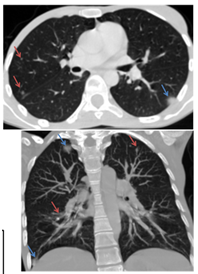

Figure 4 CT scan: (A-B) heterogeneous hyper dense mass in the thigh muscles. (C-D) Masses (blue arrow) intra parenchymal and sub pleural scattered in the 02 pulmonary fields with speculate contours-secondary locations.